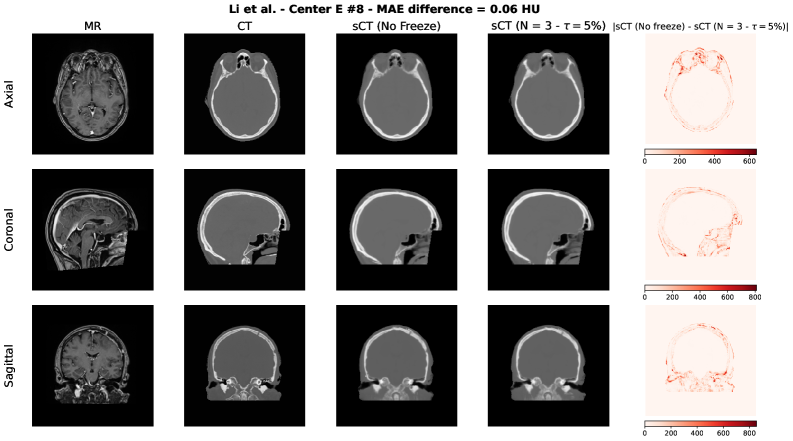

To qualitatively assess the potential impact of the adaptive freezing strategy on the generated synthetic CTs (sCTs), we conducted a visual comparison between the sCTs obtained with and without the proposed methodology. For each model employed in the study, we selected two representative test cases based on the following criteria:

• The case with the minimum difference in terms of MAE, thus the lowest difference between the sCTs MAE generated with and without adaptive freezing.

• The case with the maximum difference in terms of MAE, thus the highest difference between the sCTs MAE generated with and without adaptive freezing.

Each figure presents the following for the axial, coronal and sagittal plane of the central slice:

1. 1.

Input MR image;

2. 2.

Ground-truth CT image;

3. 3.

sCT generated without adaptive freezing;

4. 4.

sCT generated with the proposed adaptive freezing, using 𝒩=3\mathcal{N}=3 and τ=5%\tau=5\%;

5. 5.

Absolute difference map between the two sCTs.

Figure S6: Spadea, Pileggi et al. architecture [37] – Maximum MAE difference case.

Refer to caption

Across all models and both selected cases, no relevant and systematic structural differences were observed. The differences highlighted in the absolute difference maps and the variation in MAE are attributable to the stochastic nature of the training process (e.g., batch shuffling and optimization path variability) rather than the direct effect of the adaptive freezing mechanism.

This findings are aligned with the results observed in terms of MAE, PSNR and SSIM presented in this study.